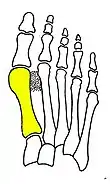

First metatarsal bone has moved aside

Fig. 1b: First metatarsal bone has moved aside

Primus varus deformity

Primus varus deformity is the leaning of the first metatarsal bone away from the second metatarsal and towards the opposite foot (Fig. 1). As it leans over, its head sticks out to form the bunion bump and it also widens the forefoot to cause shoes feeling too tight. Thus when bunion pain becomes unmanageable, surgical correction is to narrow the forefoot by repositioning of the first metatarsal head back to its normal position. This can be done by osteotomy (bone-breaking), soft tissue (non-osteotomy) or fusion techniques.